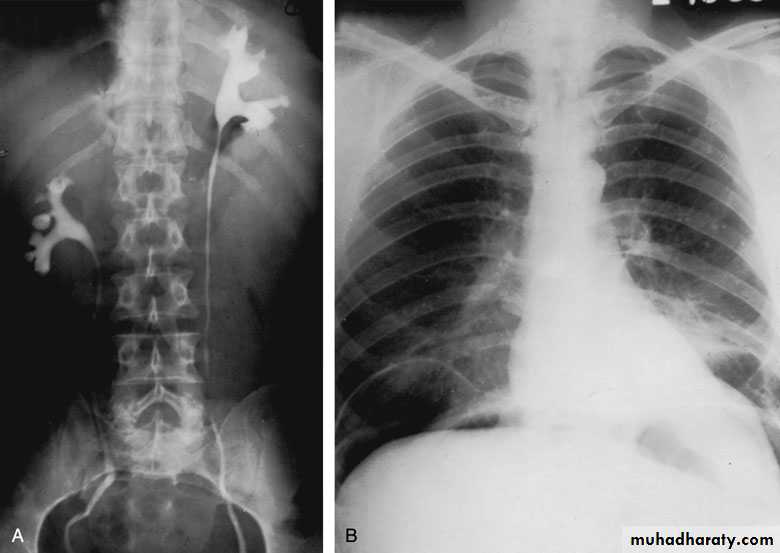

Postcaval (Retrocaval) ureter (Preureteral Vena Cava )

The right ureter pass behind the inferior vena cava

This might causes obstruction

Vascular abnormality

Incidence: about 1 in 1500Although it is congenital, most patients present at 3rd or 4th decade.

Diagnosis: IVU

Treatment:

surgical correction involves ureteral division, with relocation and ureteroureteral or ureteropelvic reanastomosis,

usually with excision or bypass of the retrocaval segment, which can

be aperistaltic